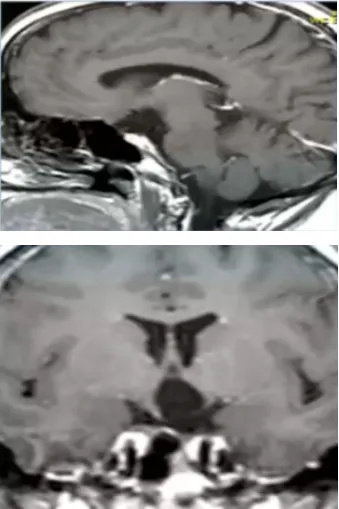

在父母的陪伴下他们来到医院就诊,医生听完了Rolla的描述,建议她前往神经外科进行脑部MR核磁检查,Rolla的这一系列症状很可能是脑子是有肿瘤“作祟”。而果不其然,检查过后Rolla疑似视神经-下丘脑胶质瘤,肿瘤主要累及下丘脑。

▼术后MRI,显示解剖性全切除